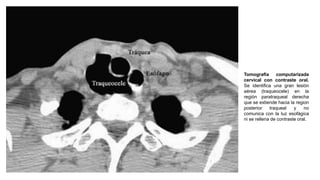

Tomografía computarizada

cervical con contraste oral.

Se identifica una gran lesión

aérea (traqueocele) en la

región paratraqueal derecha

que se extiende hacia la region

posterior traqueal y no

comunica con la luz esofágica

ni se rellena de contraste oral.